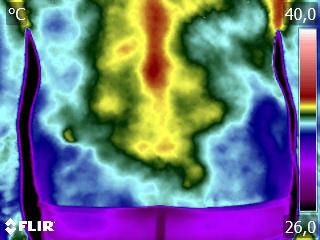

Como no caso do termograma apresentado, de um paciente do sexo masculino, 79 anos, com múltiplas comorbidades, que apresentava dor torácica e cervical. A Análise Termofuncional evidenciou alterações térmicas compatíveis com o quadro clínico, respeitando a individualidade biológica e o contexto global do paciente.

Essas informações não configuram diagnóstico médico, mas qualificam a avaliação funcional, fortalecendo o raciocínio clínico e promovendo profissionalismo no desfecho do caso.

A termografia, aplicada dentro da técnica Termofuncional, não é método diagnóstico isolado, mas um método complementar de análise funcional, dentro das atribuições legais.